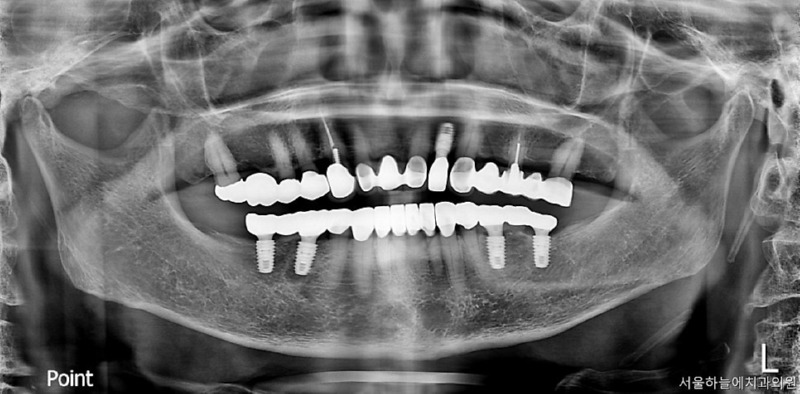

처음 내원 당시 엑스레이와 구강 상태를 보면

앞니는 파절되어 있었고

아래 어금니가 없는 기간이 길어

위 치아와 잇몸이 맞닿을 정도로 공간이 부족,

아래 앞니 역시 심하게 마모된 상태였습니다.

앞니 부위 임플란트 1개 식립

아래 양쪽 어금니 부위 임플란트 각 2개 식립

마모가 심한 아래 앞니는

크라운 치료를 통해 교합 높이 조정

이후 아래 어금니 임플란트 보철물 장착